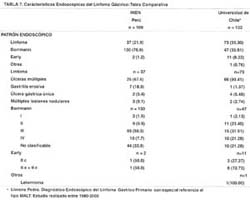

En la Tabla N° 5, se analizan las características endoscópicas de los pacientes con Linfoma Gástrico. El patrón endoscópico se ha divido en tres partes respecto al diagnóstico al ingreso de los pacientes, esto es: diagnóstico de Linfoma Gástrico, diagnóstico de cáncer gástrico avanzado tipo Borrmann y diagnóstico de cáncer gástrico temprano o early. Se identifica claramente que la predominancia de los pacientes con Linfoma Gástrico, pertenecen al denominado cáncer avanzado tipo Borrmann (76.9%). De la misma manera, el patrón endoscópico correspondiente al Linfoma Gástrico corresponde aproximadamente a 1 de cada 5 pacientes diagnosticados y el aspecto del tipo early fue identificado sólo en 2 casos. El patrón endoscópico del Linfoma a su vez fue dividido de la siguiente manera: úlceras múltiples, gastritis erosiva, úlcera gástrica y lesiones nodulares. Las úlceras múltiples son las más frecuentes dentro del presente patrón endoscópico (67.7%), y probablemente sean las lesiones más representativas de esta entidad para hacer con certeza un diagnóstico precoz de la misma.

Cuando se analiza el aspecto del Linfoma Gástrico diagnosticado al ingreso como cáncer gástrico avanzado tipo Borrmann, el aspecto de la neoplasia maligna tipo Borrmann III, es el más frecuente con el 50% de los casos, seguido del tipo No Clasificable (tipo V, según la denominación Japonesa), con el 33.8% de los mismos. El aspecto del cáncer gástrico tipo Early o Temprano para el Linfoma Gástrico, incluyó en la presente serie a dos pacientes, ambos con lesiones básicamente deprimidas tipo IIC (mixta una de ellas). La localización del Linfoma Gástrico es más frecuente en el cuerpo, sea de manera individual (18.3%), o de manera combinada, tanto en la forma del polo superior (11.8%), como del polo inferior (42.6%), respectivamente. A fin de encontrar la localización que con mayor frecuencia se encuentra en el Linfoma Gástrico, hemos reunido a todos los pacientes que tienen más de una localización con los que tienen una sola, siendo la probabilidad de compromiso del cuerpo respecto al antro de 123/91. El compromiso de todo el estómago alcanza el 13.6% y el compromiso exclusivamente del antro, llega al 11.2%. La extensión de la enfermedad a esófago se da en 10 pacientes y a duodeno en 8 pacientes, no teniendo dicha característica la mayoría de los pacientes que representaron el 89.3%. Finalmente, de los 77 pacientes evaluados en búsqueda del helicobacter pylori, se encontró positividad en el 62.3%, siendo negativos para Helicobacter pylori el 37.7% de los pacientes.

En la Tabla N° 7, se realiza un análisis comparativo con una serie de Chile que recolecta 132 pacientes de diferentes centros en 23 años (1980 - 2003), lo que nos sirve como elemento de contraste para la presente serie de nuestro instituto con 169 pacientes en 5 años (1,995– 2,000).

Lo primero que vale la pena resaltar es el idioma común empleado en la terminología de ambas casuísticas (46). En general, la serie de Chile, tiene aproximadamente la mitad de sus pacientes catalogados como Linfoma Gástrico, respecto a nuestra serie en la cual 1 de cada 5 pacientes tiene dicho diagnóstico. En el INEN el Linfoma Gástrico es catalogado como cáncer gástrico avanzado tipo Borrmann en el 76.9% respecto a la serie de la Universidad de Chile, con el 35.61%, estando en ambas series el aspecto del cáncer gástrico temprano tipo early en menos del 10% de los casos. Es de remarcar que cuando se refiere al diagnóstico endoscópico del Linfoma Gástrico, la característica predominante en ambas series es la forma de presentación de úlceras múltiples (67.6% en el INEN y 90.41% en la serie chilena). La variedad del aspecto endoscópico tipo cáncer gástrico avanzado no clasificable corresponde al 33.8% en nuestra serie y al 21.8% en el país del sur, siendo la más frecuente en el INEN la forma de cáncer gástrico tipo Borrmann III con el 50% de los casos y en la serie de la Universidad de Chile, 1 de cada 3 pacientes presentan dicha variedad. Si bien los casos del Linfoma Gástrico con aspecto endoscópico de cáncer gástrico temprano tipo early son infrecuentes, ambas series revelan la predominancia de la variedad deprimida tipo IIC.